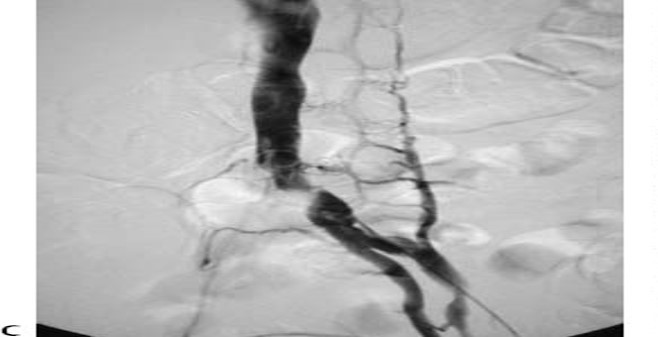

35 yoF